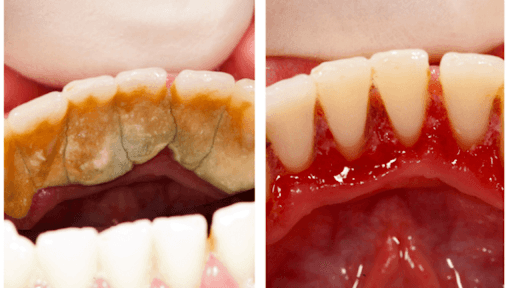

Hình ảnh cao răng

Cao răng hay còn được biết đến là vôi răng, bản chất là các muối canxi kết hợp với phosphate, hình thành từ các vụn thức ăn, muối trong nước bọt và các chất khoáng ở trong miệng. Khi sử dụng một chiếc gương và há miệng soi, bạn sẽ dễ dàng quan sát thấy tại vị trí các chân răng có bám một lớp màu vàng ố hoặc thậm chí nâu đen rất chắc chắn và đó chính là cao răng đã được hình thành.

Chính bởi tính cứng của cao răng mà rất nhiều người nhầm tưởng đó là men răng mới được hình thành và vô tư để lớp cao răng này phát triển dày lên. Trên thực tế thì ngược lại, cao răng cứng song có cấu trúc rỗng, xốp, là nơi lý tưởng cho hàng ngàn vi khuẩn trú ngụ và phát triển. Khi cao răng được hình thành, các mảng bám thức ăn có xu hướng tích tụ tại những vị trí này nhiều hơn khiến cao răng dày hơn, dần dần ăn sâu xuống chân răng. Từ đây cũng là căn nguyên gây nên một loạt các vấn đề về răng miệng như viêm nha chu, tụt lợi, viêm mòn chân răng, sâu răng,…. Chính bởi vậy mà các bác sĩ nha khoa luôn khuyên bạn nên loại bỏ cao răng và giữ răng không có những mảng bám vôi răng này.

Sự khác biệt trước và sau khi lấy cao răng